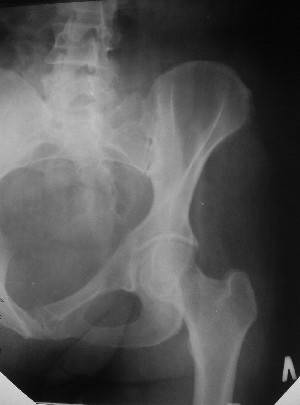

Уважаемые коллеги! Хотел-бы обсудить интерессный, на мой взгляд, случай.На консультацию пришла женщина 45 лет с отводящей контрактурой правого бедра.

Из анамнеза: в ноябре 2002г. оступилась,упалана трап самолета (на верхней площадке, сразу при выходе из салона) на правый тазобедренный сустав, а затем - вниз на землю на ноги и ягодицы. Потеряла сознание от боли. Доставлена в больницу по месту жительства, лечилась консервативно с диагнозом кокцигодиния.На рентгенограмме от 27.11.02г. вывиха копчика не определяется (снимок идентичен представленной R-грамме от28.11.03г., кроме этого есть нормальная R-грамма копчика в боковой проекции).Через три недели стала ходить, но привести правую ногу в тазобедренном суставе не могла. Сейчас ходит отведя кнаружи правое бедро и голень, как ножку циркуля (фото 1). Неврологических нарушений нет. По просьбе врачаможет на 30-40 секунд поставить ноги вместе (фото 2). При этом испытывает сильную тянущую боль и ощущение "вывернутости" в правом тазобедренном суставе. Эти ощущения заставляют вновь отвести бедро. В положении лежа разогнуть бедро полностью не может из-за болей в ягодичной мышце (фото 3). Сгибание также ограничено из-за болей (фото 4). Отведение в положении лежа возможно в том же объеме, что и стоя (фото 5). Заподозрен старый разрыв правого крестцово-подвздошного сочленения.Выполнено R-исследование и КТ(в приложении). По-поводу деформации лонного сочленения выяснен гинекологический анамнез. Роды одни, нормальные в 22 года. Из роддома выписана на 8 сутки, нарушения походки не было, R-графия таза не проводилась. Вопросы на обсуждение: 1. Диагноз либо алгоритм дальнейшего обследования. 2. Лечебная тактика (в первую очередь возможность и целесообразность оперативного лечения).

Уважаемый Юрий Алексеевич, сделаны ли пациентке более дистальные срезы КТ с захватом области тазобедренного сустава? Учитывая давность травмы, могли присоединиться и дистрофические процессы в субхондральной кости головки и впадины. Изменения в капсуле будут хорошо видны на УЗИ, особенно в сравнении со здоровой стороной. Эффективность лечебно-диагностического введения гормональных препаратов, на мой взгляд, сомнительна ввиду давности патологического состояния. При такой стойкой и давней контрактуре без операции вряд ли можно обойтись. Под наркозом амплитуда на разгибание должна увеличиться, усилить эффект можно тено-миотомиями заинтересованных групп мышц, капсулотомией + в послеоперационном периоде хорошее консервативное противовоспатлительное лечение с укладками на разгибание.Что мешает приведению пока не ясно, во встретившихся в нашей работе аналогичных ситуациях причиной был формирующийся медиальный остеофит головки, выталкивающий её из впадины.

эластичности этих мышц. В положении приведения происходит их перерастяжение, создается болевой синдром. На представленных снимках, к сожалению, эти структуры не определяются.